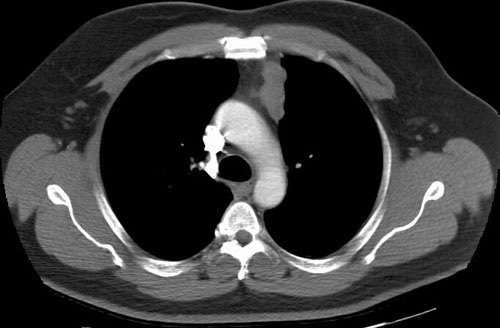

The case below is of a 9 year old girl that presented with an abnormal CXR. A large anterior mediastinal mass is demonstrated on the CT with macroscopic foci of fat attenuation. (Click image to enlarge)